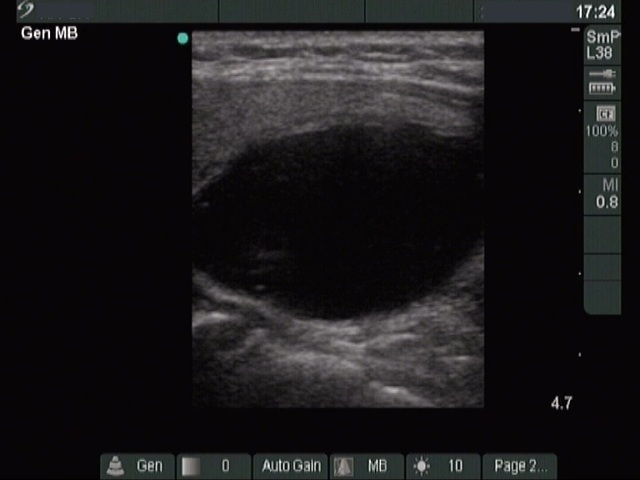

Clinical presentation: a 40-year-old woman was sent for ethanol sclerotherapy. Her thyroid cyst was evacuated three times but after each occasion the cyst got refilled within a week. FNAC resulted in a benign cystic lesion.

First row: before the first session of sclerotherapy. There was a cystic nodule in the left lobe with the dimensions of 32x27x42 mm (width x depth x length). 5 sessions of ethanol sclerotherapy was administered.